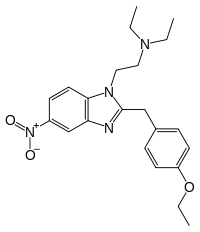

Benzimidazoles

Benzimidazoles opioids are also known as nitazenes.

- Metodesnitazene (Metazene)

- Etodesnitazene (Etazene)

- Metonitazene

- Etonitazene

- Etonitazepyne

- Etonitazepipne

- Isotonitazene

- Clonitazene